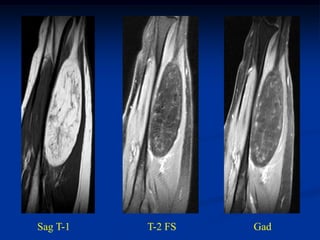

Sag T-1   T-2 FS